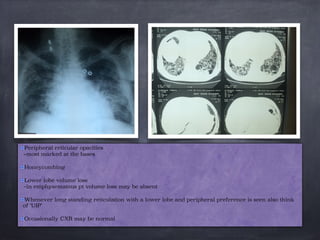

Peripheral reticular opacities

–most marked at the bases

Honeycombing

Lower lobe volume loss

–in emphysematous pt volume loss may be absent

Whenever long standing reticulation with a lower lobe and peripheral preference is seen also think

of ‘UIP’

Occasionally CXR may be normal